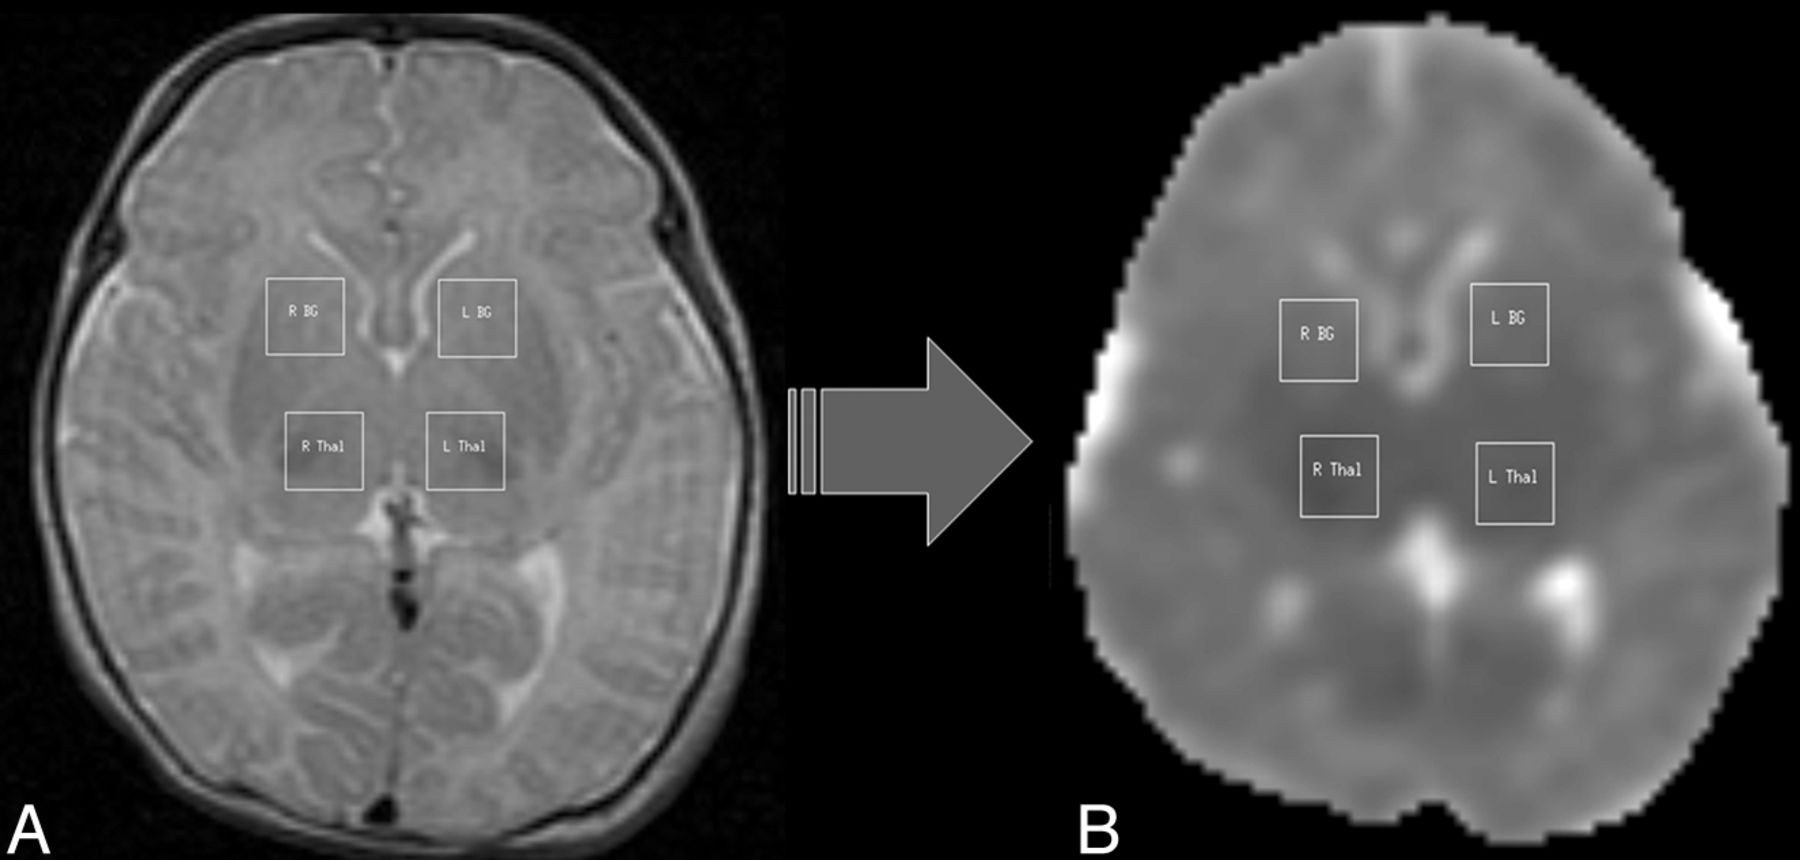

The total examination time was <1 hour. Regions of interest were drawn on T2-weighted images by using custom-built software in Interface Design Language (ITT VIS; http://www.exelisvis.com/language/en-us/productsservices/idl.aspx), bilaterally (1 cm × 1 cm2) for the BG and thalamus (Fig 1). Diffusion images were processed by using the FMRIB Software Library (http://www.fmrib.ox.ac.uk/fsl/).23 Built-in eddy current correction and masking by using the FA images were used. ADC and FA values were obtained from the BG and thalamus ROIs. The 3D MR spectroscopic imaging data were processed by using methods previously described.24 Peak-height ratios were generated for the entire brain and extracted for the specific ROIs for this study. Left and right values were averaged. Figures 1 and 2 demonstrate the ROIs from which the DTI and MR spectroscopic imaging values were measured.

Regions of interest were drawn on T2-weighted images and were later applied to diffusion maps. A, T2-weighted image (transaxial section) shows ROIs drawn bilaterally for the BG and thalamus (Thal) structures. B, ADC map shows the same ROIs applied onto the corresponding transaxial section. L indicates left side; R, right side.